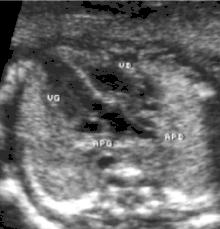

- la coupe parasternale gauche grand axe : elle montre que le vaisseau issu du ventricule gauche (le plus postérieur) se dirige anormalement vers l'arrière et se bifurque précocement. C'est donc le tronc pulmonaire et non l'aorte comme normalement ;

- les coupes sous costales qui montrent bien le trajet parallèle des gros vaisseaux et leur inversion.